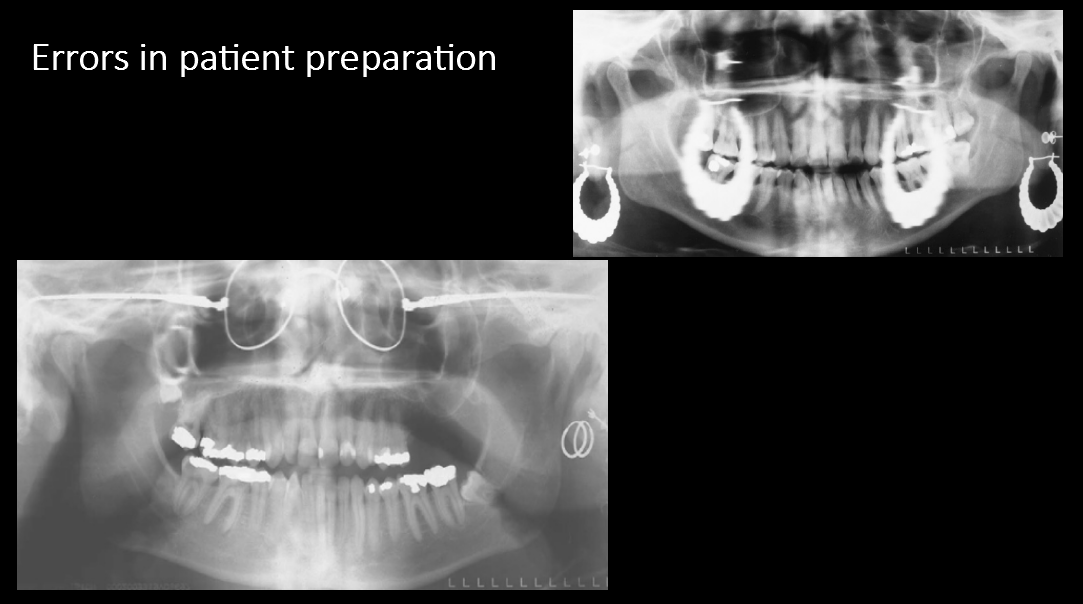

Errors in patient preparation

Image 1: Ghost image of a necklace/chain. Also jaw surgery.

Image 2: Lead apron